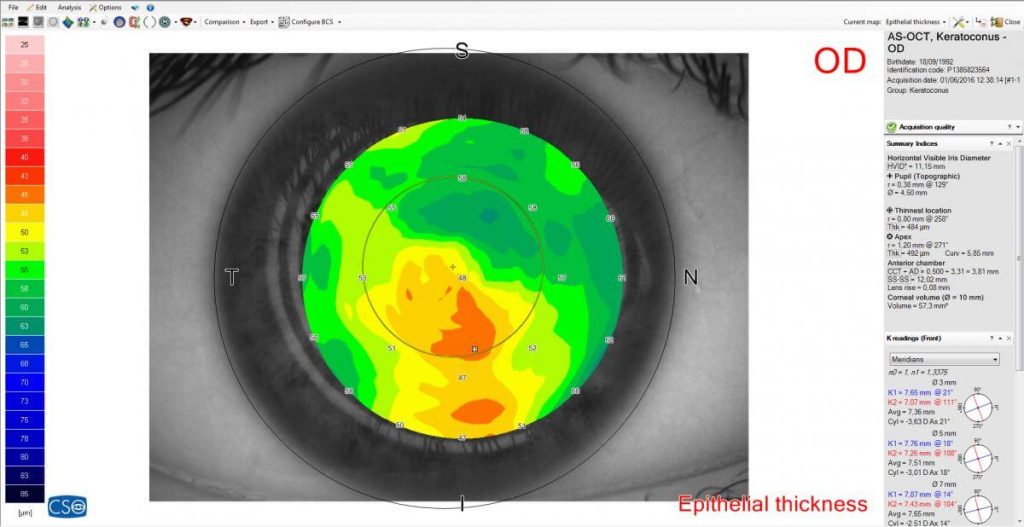

EPITHELIAL AND STROMAL MAP

MS-39 includes the advanced measurement of the epithelial and stromal layer. The epithelial masking effect is known, so knowledge of its morphology is very useful assess abnormalities of the corneal surface.